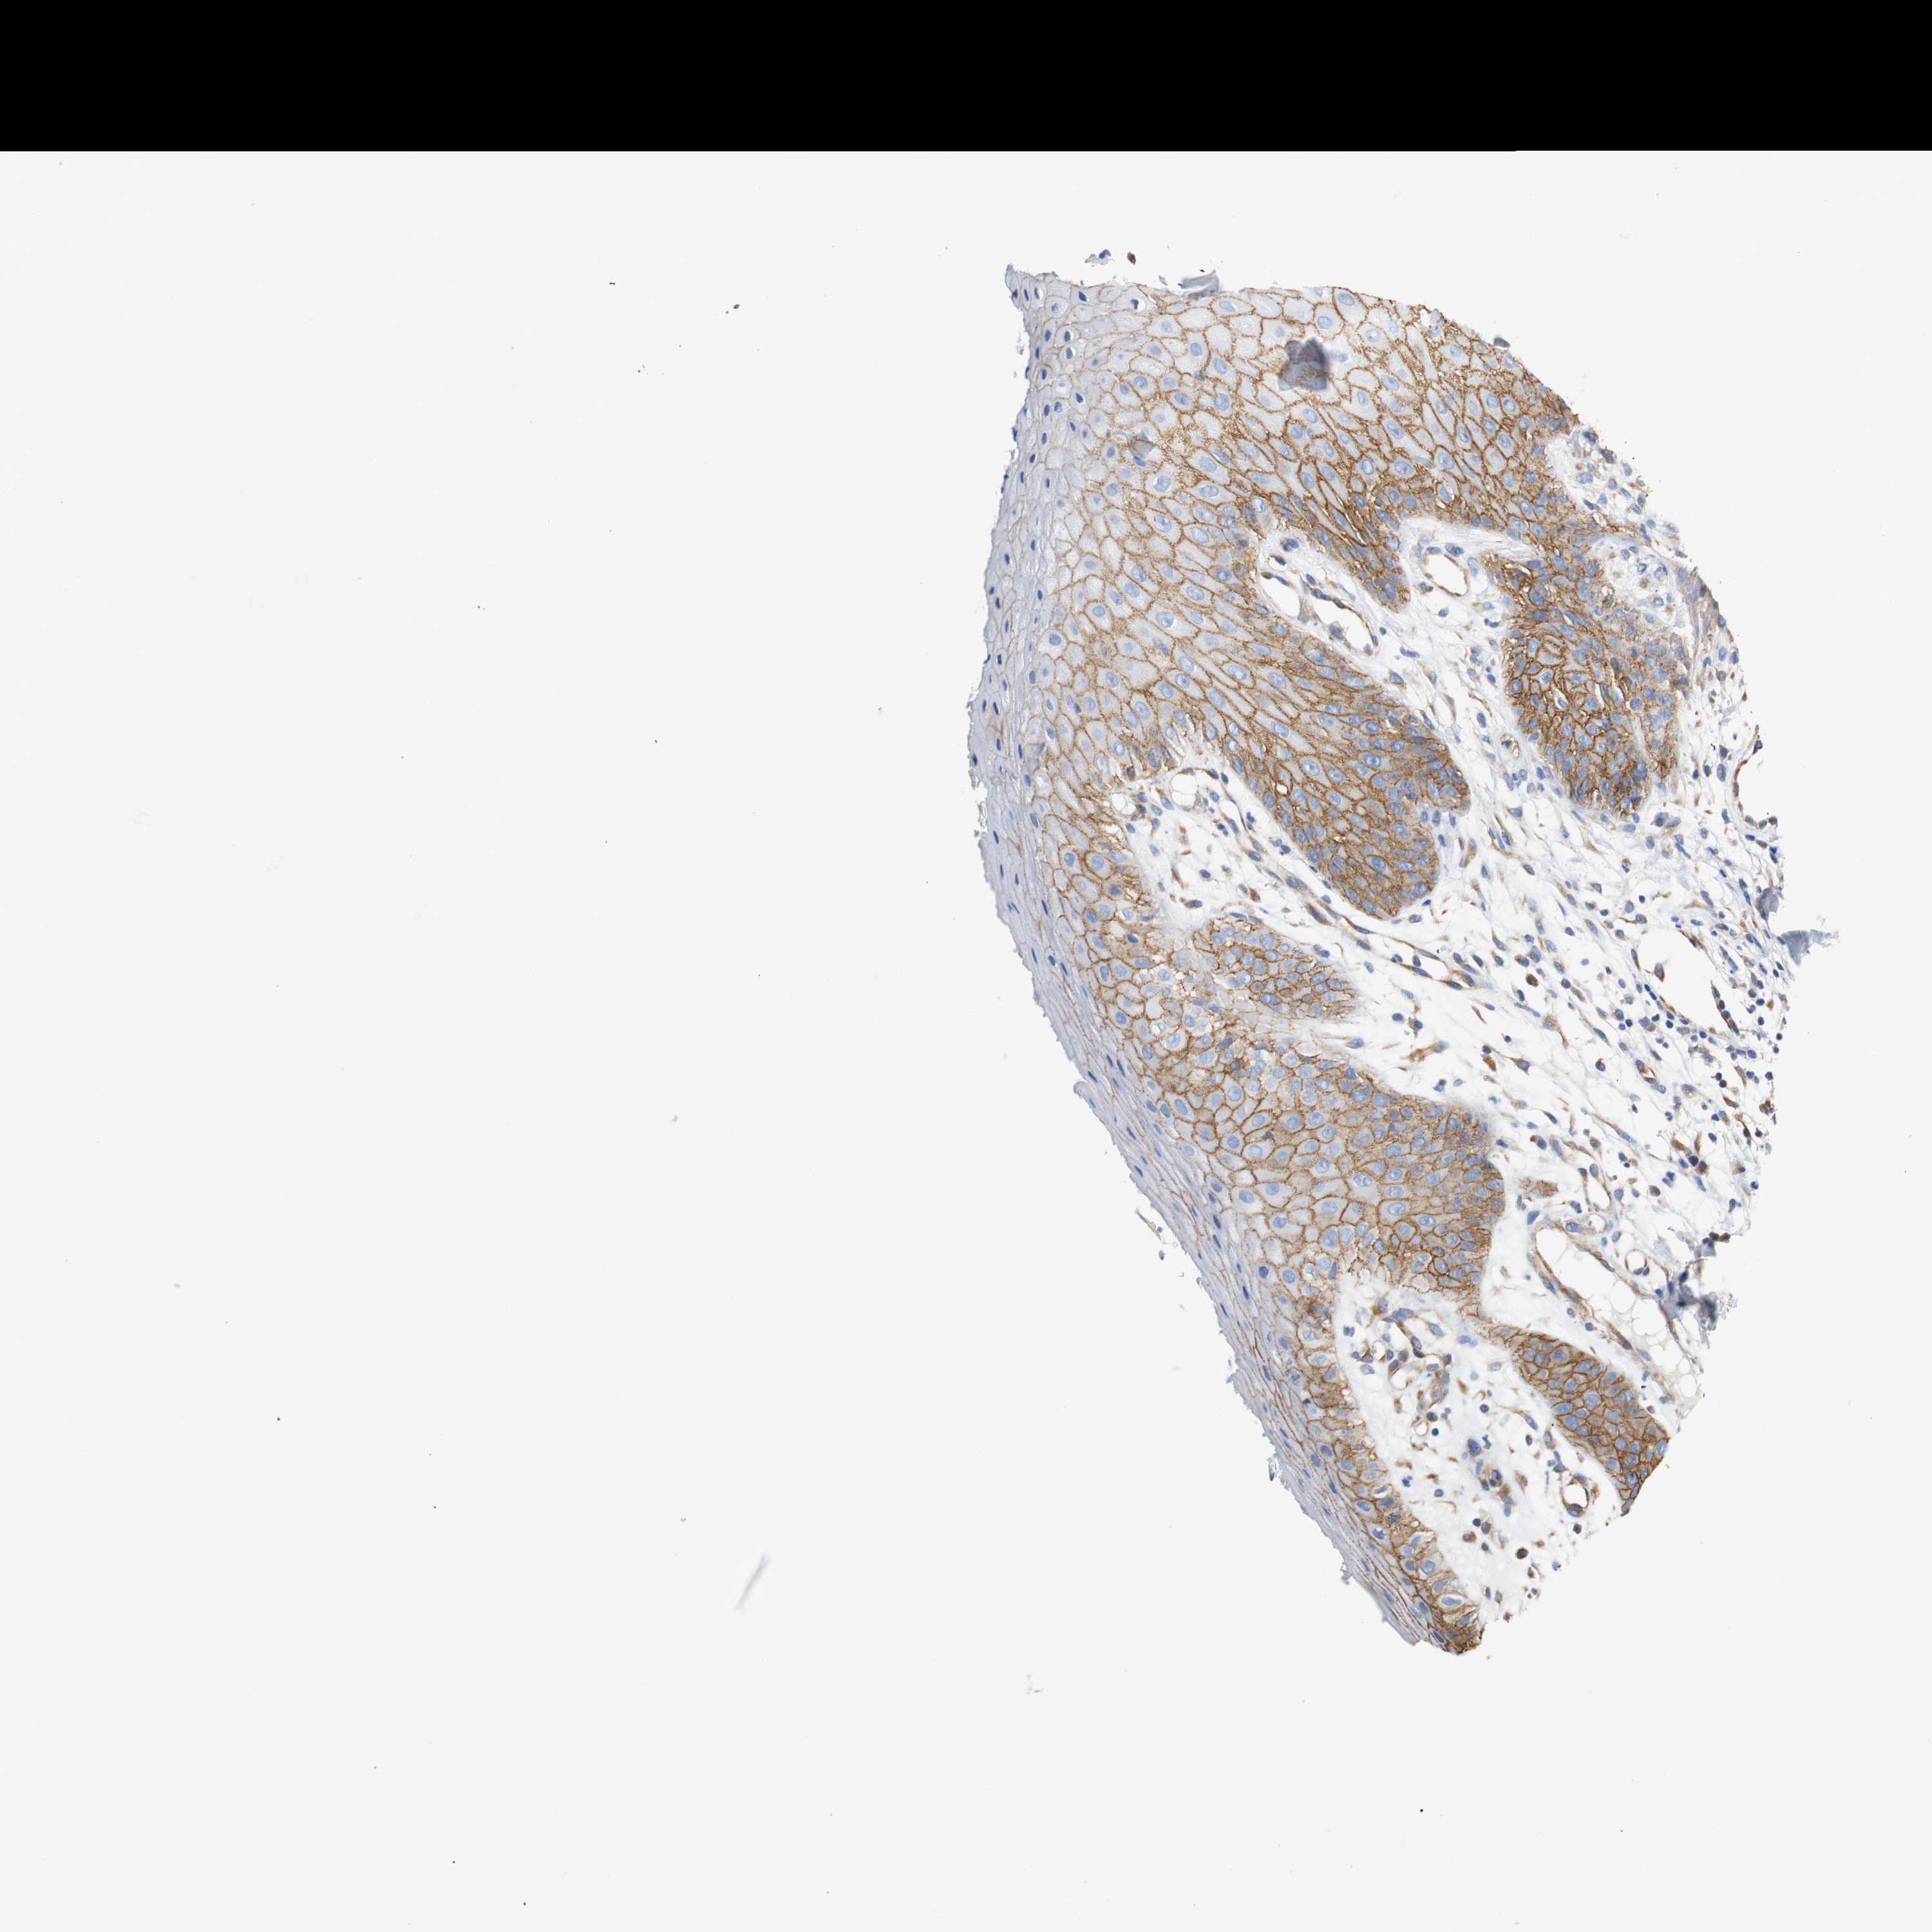

SKIN CANCER - Protein expressioni

A mouse-over function shows sample information and annotation data. Click on an image to view it in a full screen mode. Samples can be filtered based on level of antibody staining by selecting one or several of the following categories: high, medium, low and not detected. The assay and annotation is described here.

Antibody stainingi

Antibody staining in the annotated cell types in the current human tissue is reported as not detected, low, medium, or high, based on conventional immunohistochemistry profiling in selected tissues. This score is based on the combination of the staining intensity and fraction of stained cells.

Each image is clickable and will lead to virtual microscopy that enables deeper exploration of all samples and also displays staining intensity scores, fraction scores and subcellular localization as well as patient and tissue information for each sample.

Antibody CAB017027

Squamous cell carcinoma, NOS